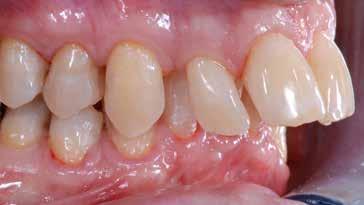

Presentazione del caso > F.V, bambino di cinque anni, presenta una malocclusione di II Classe scheletrica, III Classe dentale molare e canina destra e sinistra, morso inverso anteriore. Le arcate dentali mostrano usura degli elementi dentari anteriori a causa dell’occlusione patologica. Le linee mediane, superiore ed inferiore, sono centrate; il frenulo labiale superiore patologico per un’eccessiva estensione inter-incisale.

Dall’esame clinico si evince la III Classe dentale, l’inversione anteriore e l’over-jet negativo.

Una volta ottenuta la correzione del rapporto molare ed incisale, l’apparecchio elastodontico verrà portato dal paziente solo durante la notte per stabilizzare il risultato ottenuto e guidare l’eruzione degli elementi dentari per un totale di quattordici mesi di terapia. ad inizio trattamento :

Considerazioni > L’analisi cefalometrica ad inizio trattamento dimostra la II Classe scheletrica con protrusione del mascellare superiore e prognazia mandibolare; tendenza alla crescita verticale. L’esame clinico evidenzia una protrusione mandibolare funzionale.

55 54 ESTETICA FUNZIONE POSTURA Valori cefalometrici ad 1 anno di terapia : ANB ANB 3,8 Posizione del Mascellare SNA 91.40 Posizione della Mandibola SNB 87,60 Angolo Articolare SArGo 155,00 Angolo Goniaco ArGoMe 122,00 Angolo incisivo inf^Corpo madibolare IiMand 80,20 Angolo incisivo Sup^Base Cranica Ant. IsCran 111,05 Angolo Interincisivo II 138,00 72, 73 _ Over-bite e over-jet. 74 _ Immagine laterale destra. 75 _ Immagine laterale sinistra. Considerazioni > La terapia precoce di tali malocclusioni è di primaria importanza in quanto impedisce la formazione di malocclu-